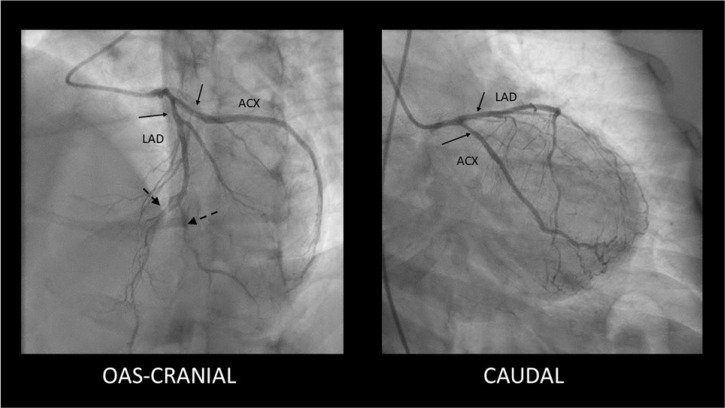

自发性冠状动脉剥离(SCAD)是急性冠状动脉综合征(ACS)的一种日益被认识的非动脉粥样硬化性原因,特别是在年轻女性中。这篇综述概述了SCAD独特的病理生理学,它与潜在的动脉病变如纤维肌肉发育不良有关,并强调了先进的血管内成像对准确诊断的关键作用。详细介绍了治疗的根本转变,有证据表明,由于血管自发愈合率高,稳定患者倾向于采用保守策略,为高风险病例保留技术上具有挑战性的侵入性干预措施。重要的是,本综述还涉及了长期结果,注意到复发率和主要不良心脏事件(MACE),持续胸痛的高患病率,以及β受体阻滞剂治疗在二级预防中的核心作用。最终,SCAD需要从标准的ACS协议转向个性化的方法,强调准确的诊断、谨慎的初始管理和警惕的长期随访。

Spontaneous coronary artery dissection (SCAD) is an increasingly recognized, non-atherosclerotic cause of acute coronary syndrome (ACS), particularly in younger women. This comprehensive review outlines SCAD's unique pathophysiology, which is linked to underlying arteriopathies like fibromuscular dysplasia, and highlights the critical role of advanced intravascular imaging for accurate diagnosis. A fundamental shift in management is detailed, with evidence favoring a conservative strategy for stable patients due to high rates of spontaneous vessel healing, reserving technically challenging invasive interventions for high-risk cases. Importantly, this review also addresses long-term outcomes, noting significant rates of recurrence and Major Adverse Cardiac Events (MACE), a high prevalence of persistent chest pain, and the central role of beta-blocker therapy in secondary prevention. Ultimately, SCAD requires a departure from standard ACS protocols towards a personalized approach that emphasizes accurate diagnosis, cautious initial management, and vigilant long-term follow-up.